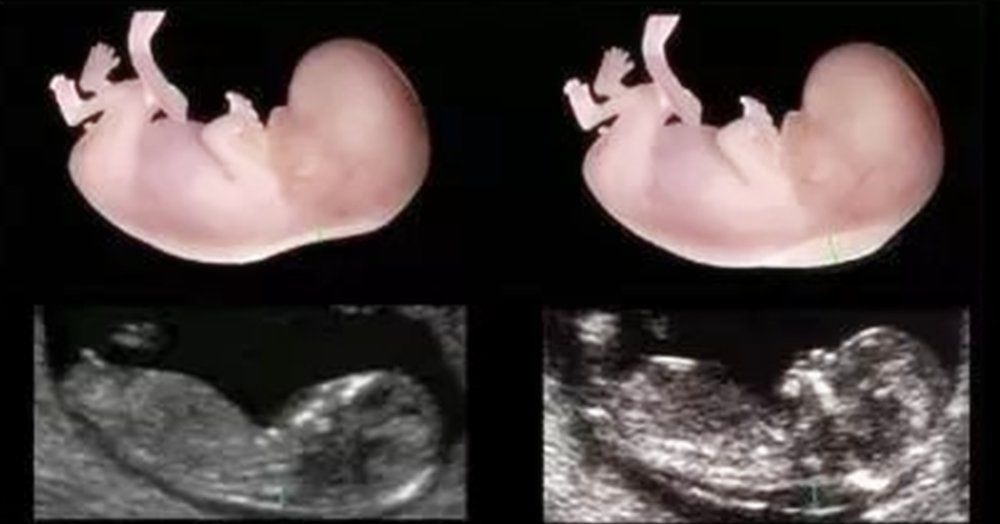

其实,现在的技术更多的是排查孩子的肢体和基因上的缺陷,在智力发育方面是检查不出来的,但是唯一例外的就是那些有唐氏综合征的孩子,在孕期便可以确定孩子出生后会有智力障碍。所以孕妈不想自己会生出来一个“傻孩子”,孕期的唐氏筛查检查是一定要做的。2)NT检查NT检查主要是通过测量胎儿颈部后方透明膜的厚度,来初步判断胎儿是否存在畸形和智力发育方面的欠缺,因此也是不能省略的。

3)大排畸检查大排畸检查是个孕期所以孕检项目中,检查胎儿部位最全面的一项检查,除了看胎儿的外观,还会检查胎儿内部器官的发育情况。产检结果并非是“百分之百”,按时产检,孩子依旧会有问题当然,很多时候,即使妈妈在孕期做了全方位的检查,但是孩子出生后仍然就给妈妈“致命一击”。孕期没有检查出来的智力问题或者一些其他的缺陷,都会让妈妈难以接受。